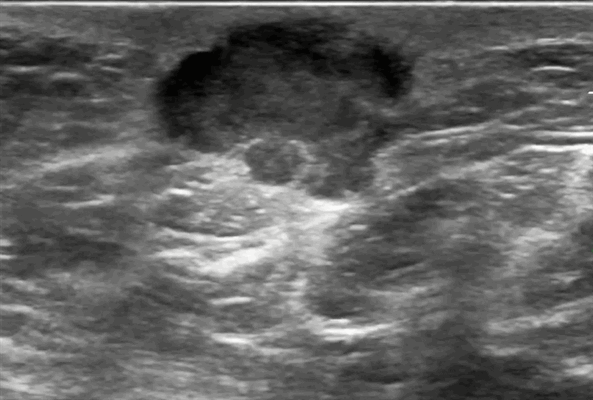

Узловая форма рака грудной железы на УЗИ может обнаруживаться в виде единичных или множественных узлов. Размеры опухоли обусловлены темпами роста и временем их выявления. Имеется особенность ультразвуковых срезов двух морфологических вариантов узловой формы раков грудной железы — четко отграниченных опухолей с экспансивным характером роста и плохо отграниченных раков (скиррозного или звездчатого) с инфильтративным типом роста. При экспансивном (раздвигающем) типе роста опухоли имеют правильную округлую или овальную форму, хорошо очерченные или немного размытые контуры. Опухоль проникает в окружающие ткани, при этом происходит их сжатие и деформация, но не разрушение.

При ультразвуковых исследованиях при округлых и овальных формах контуры опухолей обычно бывают ровными во всех случаях. Границы опухолей при овальной форме чаще бывают четкими. В большинстве случаев, когда встречается округлая форма, а размеры опухоли не превышают 3 см, границы также бывают четкими. При увеличении размеров патологических образований четкость границ фиксируются неравномерно, так в некоторых срезах трудно визуализировать контуры либо из-за появления акустической тени, либо из-за отсутствия четкой дифференциации края опухоли.

При воздействии давлением датчиком на опухоль с экспансивным характером роста имеется минимальное изменение ее формы и симптом «соскальзывания» или смещение образования среди окружающих тканей, что не наблюдается при компрессии инфильтрирующих форм рака. При ультразвуковом исследовании ориентация длинной оси образования по отношению к ультразвуковому лучу. Наиболее часто обнаруживаемая ориентация опухоли при исследовании — неопределенная (60%), более редко встречается вертикальная ориентация (30%) и еще реже — горизонтальная (10%), которая определялась лишь при овальной форме злокачественного новообразования. На рентгеновской маммограмме узловая форма рака грудной железы определяется в виде образования неправильной формы, с нечетким контуром.

При изучении эхогенности опухолей выявлено, что наиболее часто наблюдается однородная структура. При проведении ультрасонографии необходимо помнить, что акустически гомогенная ткань патологического образования при раке молочной железы всегда бывает гипоэхогенной по сравнению с окружающей паренхимой. При этом тенденция к неоднородности внутри опухоли появляется по мере увеличения размеров образования. Так, для опухолей размером до 4 см более характерна однородная их структура, более 5 см — неоднородная.

Узловые формы хорошо отграниченных раков содержат медуллярный, муцинозный, папиллярный, ряд протоковых раков и саркомы. На ультразвуковом исследовании видно, как эти опухоли в процессе своего роста сдавливают окружающие ткани, но они практически не вызывают или вызывают минимальные фиброзные изменения окружающих тканей. На УЗИ молочной железы структура может быть различной и меняется от наличия участков некроза, фиброза, кальцинатов, опухолевых сосудов. С помощью эхографии трудно отличить эти хорошо отграниченные раки от доброкачественных солидных образований.

Медуллярные раки имеют округлую или дольчатую форму кистозно-солидного строения, хорошо отделены от окружающих тканей, не имеют капсулы. По мере роста медуллярного рака формируются анэхогенные зоны некроза с участками организовавшихся и свежих кровоизлияний. Часто на УЗИ выявляется анэхогенный ободок, который по данным морфологической оценки отвечает за место активного опухолевого роста. Дистальное усиление связано с наличием большего количества солидного компонента опухоли с меньшим содержанием (менее 25%) соединительнотканных структур. При увеличении размеров опухоли кпереди от образования может появиться широкий ободок повышенной эхогенности. При больших размерах опухоль закрепляется к передней грудной стенке, может изъязвляться. Опухоль маленьких размеров клинически похожа на фиброаденому. Кроме того, надо помнить, что медуллярные раки при ультразвуковом исследовании молочных желез не часто обнаруживаются после менопаузы.